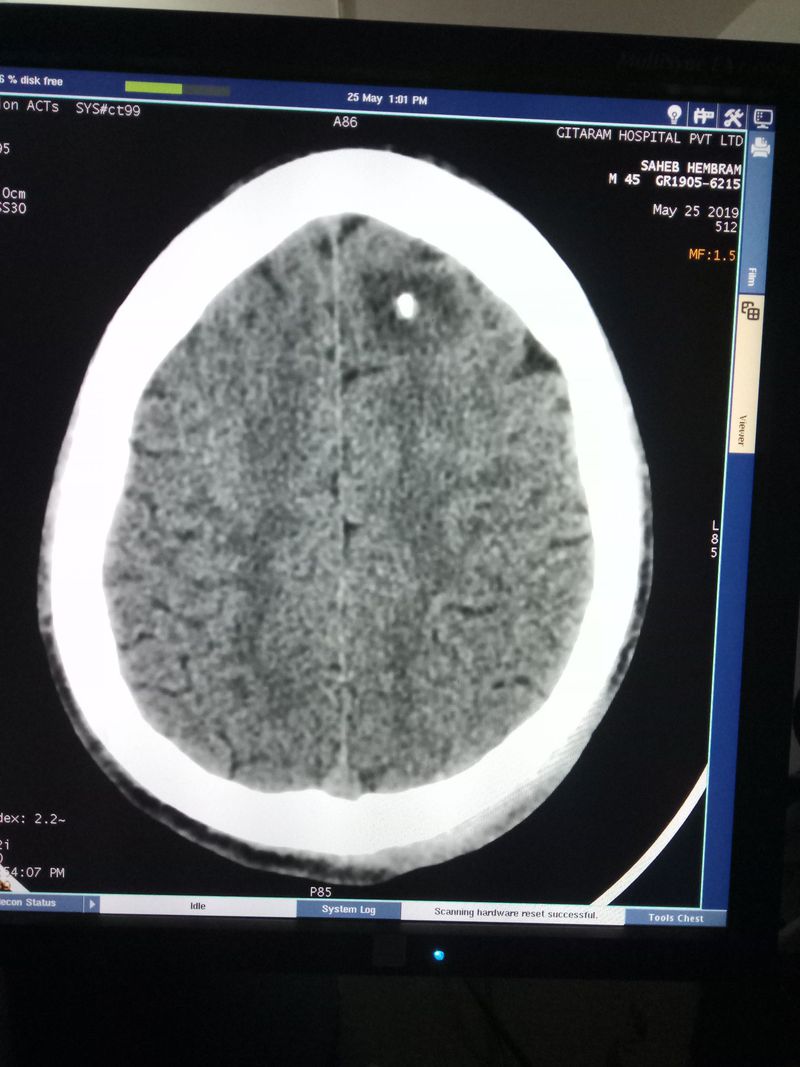

Age 32 yrs.. Male

History.. Weaknesses

Headache

Vomiting

Weakness

Subdural hematoma

Calcification or tumor?